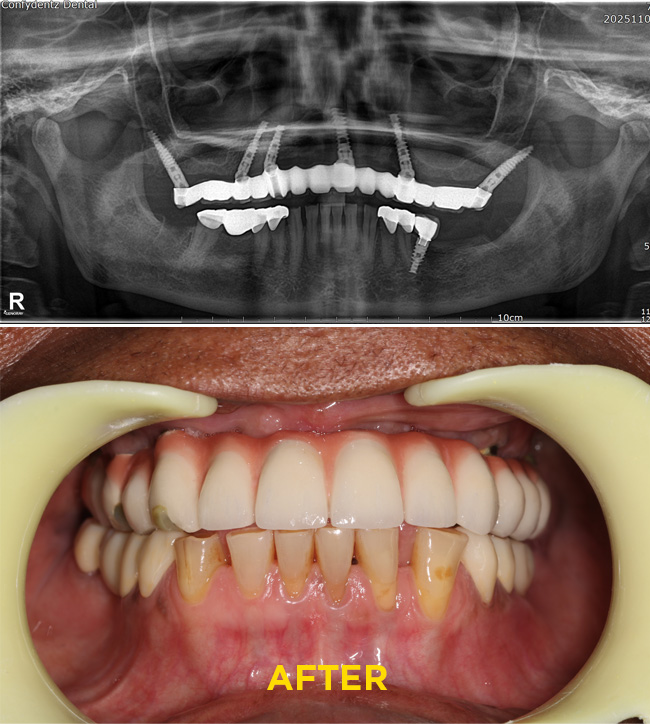

Case - 1